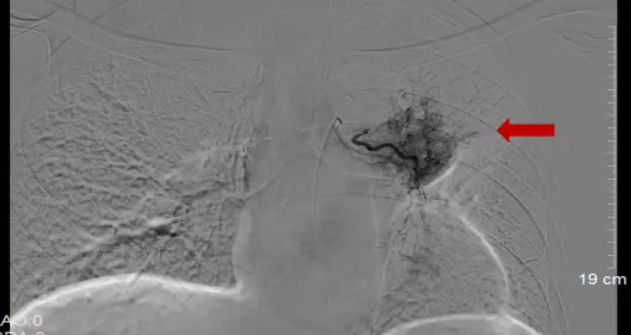

今年1月,患者出现活动后气促不适,来院复查胸部CT提示左上肺不张;支气管镜检查显示左肺上叶支气管增厚,活检病理提示肿瘤复发。患者为局部复发,相关检查未发现其他部位转移。鉴于左肺病灶已接受局部放疗,且放疗后1年内肿瘤复发,短期内无法再次行放疗。经我院胸部肿瘤内科与肿瘤与血管介入微创治疗中心医疗团队联合会诊评估后,为其制定了个体化治疗方案——实施经导管支气管动脉栓塞化疗术。

患者先后接受两次经导管支气管动脉栓塞化疗术。治疗后,患者活动后气促症状显著缓解;今年3月复查胸部CT显示,左上肺远端阻塞性炎症较前显著改善,病情得到控制。

支气管动脉化疗栓塞术(bronchial artery chemoembolization,BACE)作为一种微创介入治疗手段,通过动脉导管向肿瘤供血动脉直接输注高浓度化疗药物,同时开展血管栓塞操作。作为一项相对成熟的姑息性微创治疗技术,BACE已被应用于肺癌的局部治疗。其治疗机制体现在:经肿瘤供血动脉(以支气管动脉为主)直接灌注化疗药物,既能提升肿瘤区域的药物浓度、增强细胞毒作用,又借助肝脏等器官的首过代谢显著降低全身循环中的药物浓度;同时,BACE具备血管阻断效应,通过栓塞材料堵塞肿瘤滋养动脉,促使肿瘤组织缺血性坏死。此外,该技术还拥有微创高效、损伤小、恢复速度快、可重复性强等显著优势。